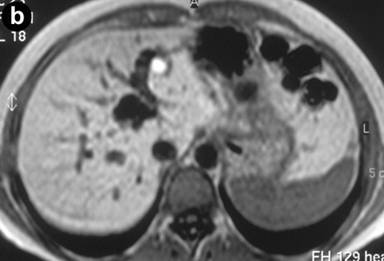

A 27-year-old female underwent a cholecystectomy for lithiasis. The patient was successively evaluated for diffuse and recurrent abdominal pain; no alcohol and/or smoking habits were reported. Laboratory measurements of total bilirubin and pancreatic amylases were unremarkable. Abdominal ultrasound was carried out which showed multiple hepatic and pancreatic cystic lesions; a dynamic enhanced CT scan confirmed the presence of multiple liver and pancreatic cystic lesions, but, in particular, the differentiation between simple hepatic cysts and cystic ectasia of the biliary ducts suggestive of Caroli’s disease was not reached. Therefore, MRI was requested to characterize the liver lesions and it was performed acquiring T1- and T2-weighted sequences integrated with T2-hydrographic images to specifically evaluate the biliary tract in axial and coronal views. MR cholangiography after intravenous administration of mangafodipir trisodium (Teslascan®, Nycomed, Amersham, Oslo, Norway), was also performed using T1-weighted sequences. Turbo spin echo T2-weighted images in axial and coronal views showed multiple hyperintense focal lesions in the left lobe of the liver, typical of cystic lesions, as well as multiple pancreatic cysts of the tail and saccular ectasia of the main biliary duct (Figure 1). T2-hydrographic dedicated images confirmed these findings, but certain imaging signs for a differential diagnosis between simple hepatic cysts and biliary cysts were not identified (Figure 2). However, the enhanced mangafodipir trisodium T1-weighted MRI clearly showed that some of the liver cysts concentrated mangafodipir trisodium contrast medium, thus demonstrating that these enhanced cystic lesions were in communication with the biliary ducts providing imaging criteria consistent with a diagnosis of Caroli’s disease (Figure 3). A segmental hepatectomy specimen demonstrated dilated simil-cystic intrahepatic ducts of the IV segment corresponding to a diagnosis of Caroli’s disease.

Figure 1. Conventional turbo spin echo T2-weighted axial (a., b. and c.) and coronal (d.) MR views show multiple cystic lesions in the left liver lobe as well as in the pancreatic tail. Saccular ectasia of the main biliary duct is also depicted. |